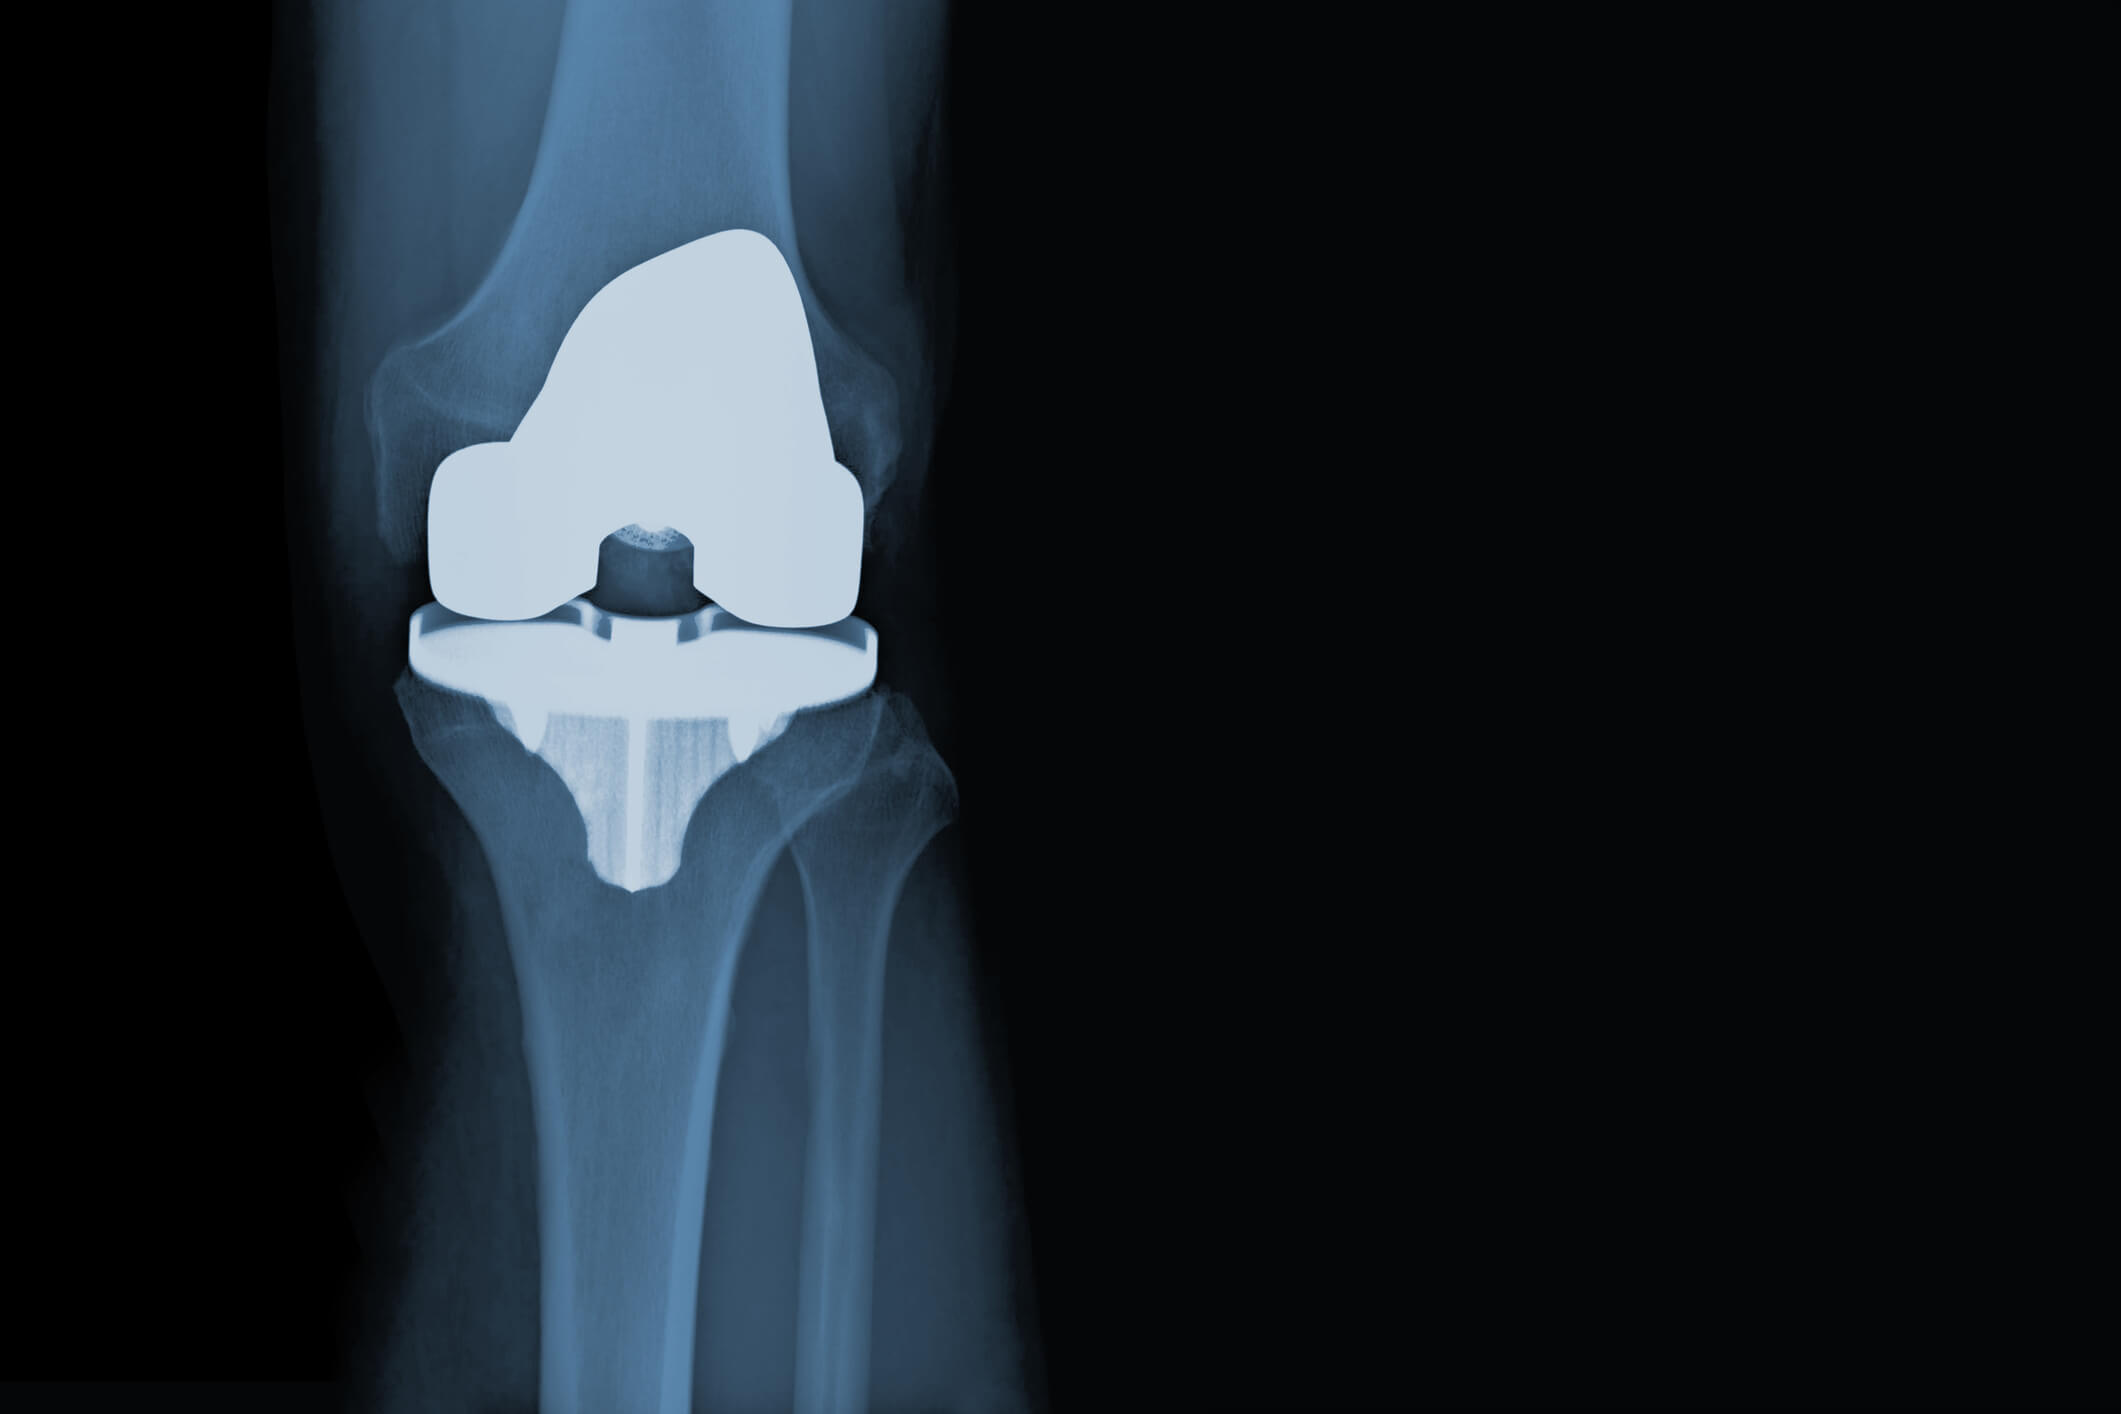

Knee Replacement Parts Recall . a standard total knee replacement has 4 parts. letters state reason for recall, health risk and action to take: exactech recalled polyethylene inserts for knee and ankle replacements due to oxygen exposure that. knee insert and acetabular system parts were swapped within inner pack prior to the product being sealed within the tray, which. learn about the reasons and consequences of knee replacement recalls by manufacturers such as depuy, zimmer biomet and stryker. hss informs patients who received exactech knee, ankle or hip implants between 2004 and 2021 that the company recalled some components due to. These include the femoral component, tibial tray, patellar.

Total Knee Replacement